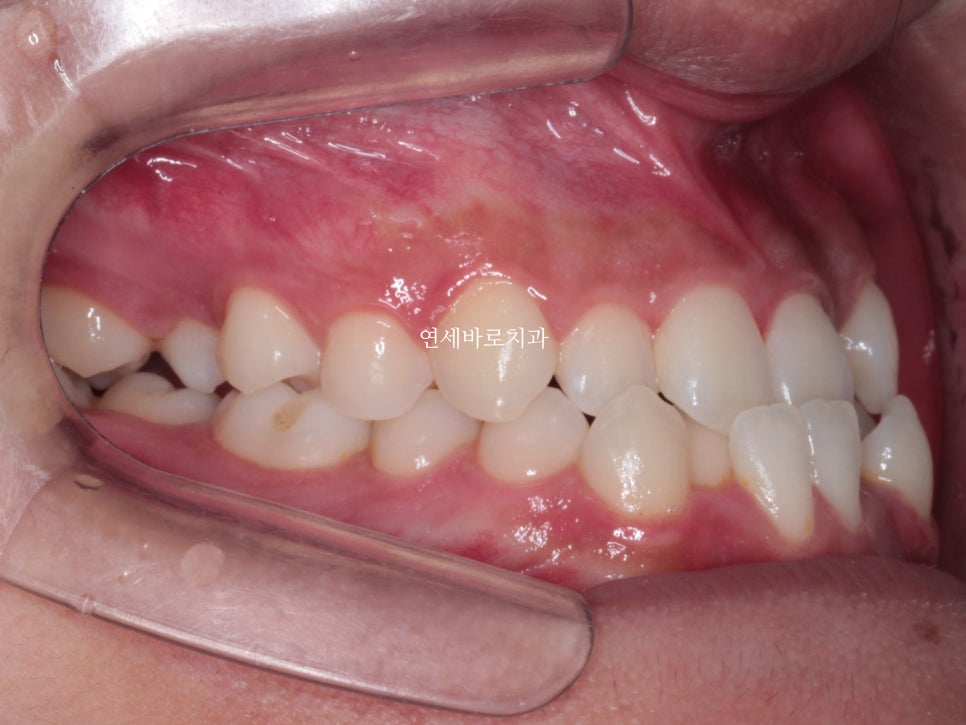

약 2년전쯤 왔던 친구입니다.

골격적인 3급 부정교합, 즉 '주걱턱'양상을 보이고 있었습니다.

또한 위아래 덧니가 심했어요.

특히 위쪽 어금니쪽은 치료가 쉽진 않았습니다.